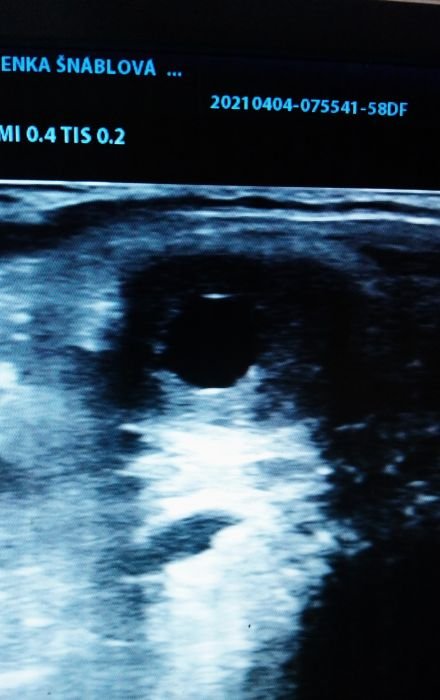

Dominantní folikul krátce před ovulací

Přesné zjištění ovšem bez dalšího následného USG vyšetření není možné, je tedy třeba USG vyšetření opakovat. Vím, že se opakuji, ale tohle je velmi důležité: při inseminaci chlazeným (čerstvým) semenem není potřeba vyšetření USG mnoho, ale je důležité po inseminaci zkontrolovat, zda klisna zovulovala. Při inseminaci mraženým semenem se USG vyšetření provádí přibližně každých 6 hodin (bavíme se o době těsně před ovulací, kterou předpokládáme dle velikosti a stavu folikulu 4,5 a více cm). V ideálním případě si zkušený technik pohlídá ovulaci klisny tím, že při velikosti folikulu cca 3,5 – 4 cm aplikuje hCG. K vlastní inseminaci pak dochází v době před ovulací (čerstvé semeno), v případě využití mraženého semene pak ideálně těsně před či po ovulaci. Pokud máme klisnu po ovulaci (zjištěno USG), další vyšetření, nyní již na graviditu, lze provést již od 13. dne, ideálně však 16. den po ovulaci, kdy dochází k tzv. nidaci oplozeného vajíčka, tj. uchycení na jednom místě v děložní sliznici.

Velmi často využívaným stimulantem je hCG (glykoproteinový hormon ze skupiny gonadotropinů). HCG zkracuje estrální (říjový) cyklus. Používá se, pokud je vidět na jednom z vaječníků dominantní folikul o velikosti minimálně 35–40 mm. K ovulaci obvykle dochází během 36–48 hodin. V této době je ideální klisnu inseminovat. Pokud inseminujete chlazeným spermatem, stačí v době po aplikaci hCG jedna dávka spermatu. Je ovšem nutné si zkontrolovat, zda klisna opravdu zovulovala do uvedených 48 hodin. V případě použití mraženého spermatu je ideální inseminovat těsně před či spíše těsně po ovulaci.